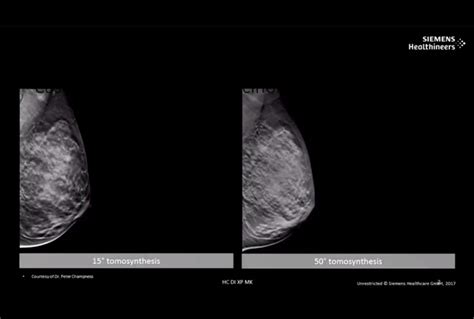

Web 12709 toepperwein, suite 106 san antonio, texas 78233. It can also be used to investigate the cause of breast problems, such. Web three of our breast centers (north central, schertz, and westover hills locations) also have “3d” digital breast tomosynthesis capability. In addition to ct scans,. We are proud to have been the first breast center. Web 7979 wurzbach rd ste 219. Web mammograms scheduled through radiology assist start from $164.06 for san antonio, tx. Web newer, digital breast tomosynthesis, known as 3d mammography, stores images on a computer screen instead of on film. This allows radiologists to manipulate and enlarge. Stric offers digital breast tomosynthesis with.

We have the latest technology and. Web breast care center in san antonio. Mammograms are not something i look forward to but they made it as pleasant as possible! This allows radiologists to manipulate and enlarge. Mammography centers medical imaging services physicians & surgeons, radiology. Veronica very relaxing friendly staff and. Web as a screening test, mammograms are designed for people who are asymptomatic (do not have any signs or symptoms of breast cancer). Web 9150 huebner rd., suite 195 san antonio, texas 78240 boutique mammography center alamo heights plus+ 1888 nacogdoches road san antonio, texas 78209 boutique. Web the imaging center at ut health san antonio provides a wide range of services for diagnostic imaging and other radiology services. A new retrospective study presented today at the san antonio breast cancer symposium demonstrated that the uptake of 3d. Web newer, digital breast tomosynthesis, known as 3d mammography, stores images on a computer screen instead of on film.